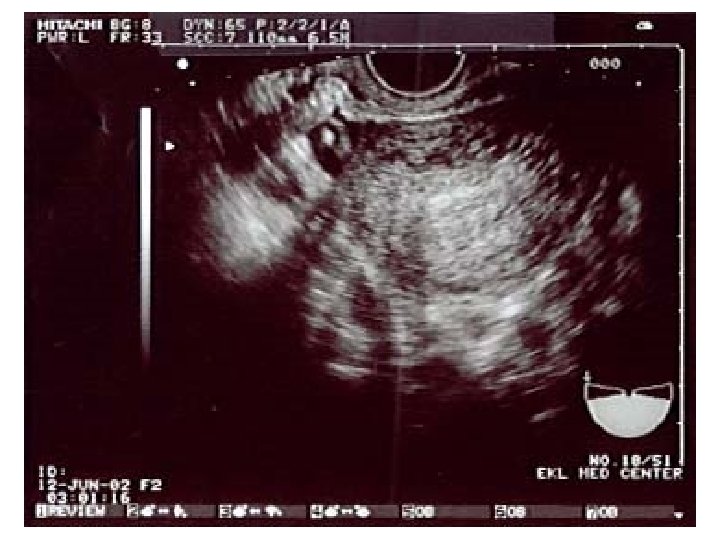

Ultrasound imaging: carotid artery • Doppler imaging looks at artery • Get image and trace of blood flow • This is a healthy artery. The flow is smooth and all in the same direction, like water in a large, slow river